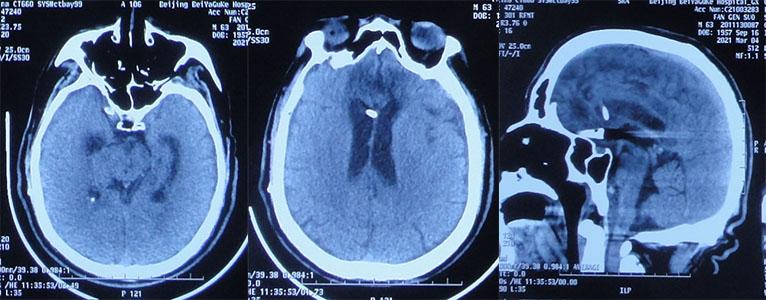

患者2020年10月16日6时30分晨起突发头晕呕吐,伴有意识不清,家属拨打120,将其送入山西省运城市某医院,急诊查头部CT示额叶脑出血伴广泛蛛网膜下腔出血、脑室内铸型( 图-1 );住入重症病房。

图-1: 2020年10月16日头部CT:额叶脑出血伴广泛蛛网膜下腔出血、脑室内铸型